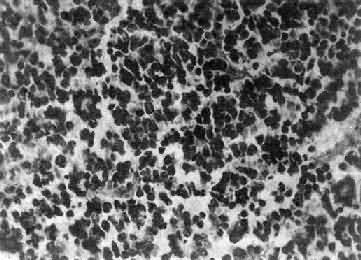

镜下,细胞大小形态一致,呈梭形或胡萝卜形,胞核圆或椭圆,染色质呈细颗粒状,核膜清楚,有核仁。细胞胞浆丰富,突起明显。细胞的排列有二种特征,一是环绕空腔排列成腺管状,形态上与室管膜腔相似,称为菊形团形成,另一是环绕血管形成假菊形团结构,细胞有细长的胞浆突起与血管壁相连(图16-25)。细胞中有神经胶质纤维,以PTAH染色在个别细胞的腔面或胞核旁可见纤毛体,后者与纤毛运动有关,是室管膜细胞的特征性结构。此外,有时还可形成乳头状结构。发生在脊髓圆锥和终丝的肿,乳头状结构轴心中的结缔组织往往富含粘液。

图16-25 室管膜

细胞为圆形或卵圆形,核染色质丰富,胞浆少,可见有细长的胞浆突起与血管相连,呈放射关,形成假菊形团